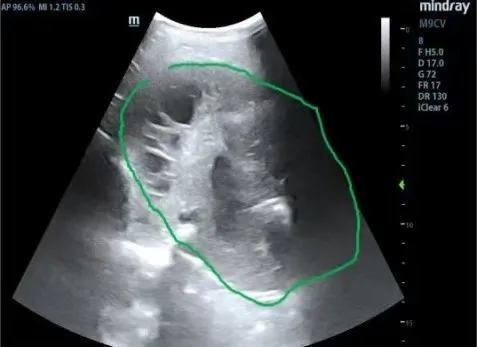

为进一步明确诊断、改善患者症状,拟行包裹性积液胸腔穿刺置管引流术。但常规胸腔穿刺引流极易造成穿刺损伤及穿刺失败风险,较以往相比因技术难度和风险高,北京“组团式”帮扶专家史淑利主治医师、青海红十字医院称多支医队员肿瘤科范得艳主治医师查看患者并综合研判患者病情后,联合超声科医生共同为患者实施了床旁超声引导下包裹性胸腔积液穿刺置管引流术。在手术过程中,称多县医院超声科医生首先利用超声设备对患者胸腔内的包裹性积液进行精准定位,清晰地确定积液的位置、范围以及最佳穿刺点。随后,由北京“组团式”帮扶专家史淑利主治医师、支医队员肿瘤科范得艳主治医师共同协助在超声实时监测下,将穿刺针准确地插入积液腔。整个过程如同一场精细的外科手术,每一个步骤都严谨而准确。手术完成后,根据患者胸水常规、生化、ADA检测对患者明确诊断为“肺结核;结核性胸膜炎”。患者胸闷、气短症状得以缓解,给予患者规范抗结核治疗、引流胸腔积液治疗。患者及家属对手术效果非常满意,对支医队员们的专业技术和精心护理给予了高度赞扬。

现代超声被誉为“看得见的听诊器”,具有快速、可靠、无创及可重复等优点。床旁危重症超声已逐渐成为现代危重症救治的重要监护工具之一,能为临床决策提供更准确、可靠的指导意义。相较于传统穿刺,床旁超声引导下的胸腹腔穿刺、血管穿刺技术,能获得更高的穿刺成功率和更低的穿刺损伤,使侵入性治疗变得更安全、有效。

包裹性胸腔积液是一种较为复杂的病症,常给患者带来严重的不适,如呼吸困难、胸痛等。传统的治疗方法往往效果有限且存在一定风险。而超声引导下的穿刺引流术为患者带来了新的希望。通过这种先进的技术手段,不仅大大提高了穿刺的准确性,减少了对周围组织的损伤,还能实时观察穿刺针的位置和进针深度,确保操作的安全性。与传统开胸手术相比,该穿刺引流术具有创伤小、患者恢复快等显著优势。